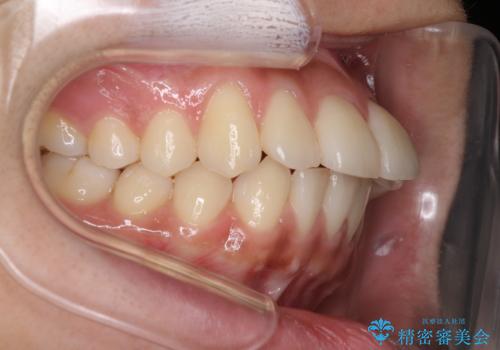

横顔をすっきりさせたい 下の前歯が1本少ない方の変則的な抜歯矯正

口元の突出感がありと、下顎の前歯が1本欠損していました。

上顎の前から両側の前から4番目の歯と、下あごの前歯を1本抜歯して、口元をすっきりさせる計画としました。